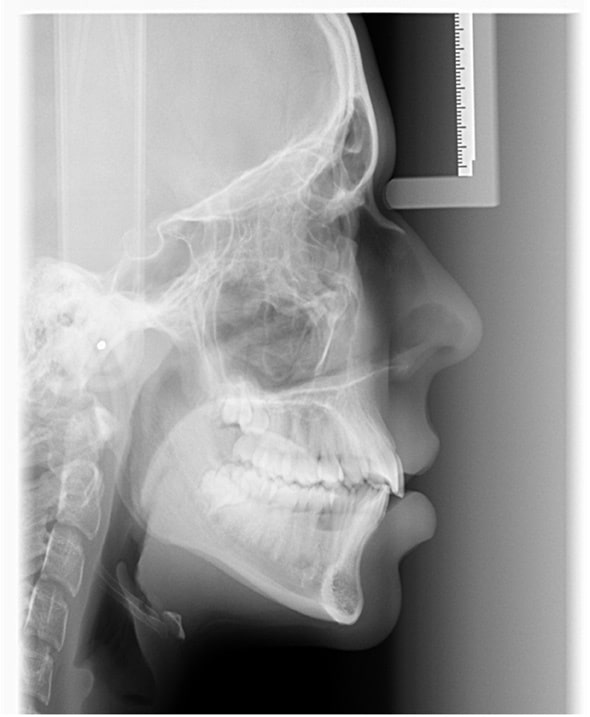

Comme pour chaque première visite, nous avons procédé à une analyse orthodontique complète : radiographies (téléradiographie latérale du crâne et orthopantomographie) mais aussi une série de photos des dents et du profil.

Les résultats de cette étude ont permis d’identifier plusieurs points-clés :

- Un manque de place marqué dans l’arcade supérieure.

- Des incisives supérieures qui penchaient franchement vers l’avant.

- Une mâchoire supérieure comprimée.

- Une ligne médiane supérieure décalée sur la gauche, ne coïncidant pas avec celle du bas.